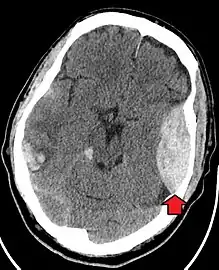

Blunt cranial trauma

The primary clinical concern with blunt trauma to the head is damage to the brain, although other structures, including the skull, face, orbits, and neck are also at risk.[8] Following assessment of the patient's airway, circulation, and breathing, a cervical collar may be placed if there is suspicion of trauma to the neck. Evaluation of blunt trauma to the head continues with the secondary survey for evidence of cranial trauma, including bruises, contusions, lacerations, and abrasions. In addition to noting external injury, a comprehensive neurologic exam is typically performed to assess for damage to the brain. Depending on the mechanism of injury and examination, a CT scan of the skull and brain may be ordered. This is typically done to assess for blood within the skull or fracture of the skull bones.[17]

Traumatic brain injury (TBI)

Traumatic brain injury (TBI) is a significant cause of morbidity and mortality and is most commonly caused by falls, motor vehicle crashes, sports- and work-related injuries, and assaults. It is the most common cause of death in patients under the age of 25. TBI is graded from mild to severe, with greater severity correlating with increased morbidity and mortality.[17][18]

Most patients with more severe traumatic brain injury have a combination of intracranial injuries, which can include diffuse axonal injury, cerebral contusions, and intracranial bleeding, including subarachnoid hemorrhage, subdural hematoma, epidural hematoma, and intraparenchymal hemorrhage.[8][17] The recovery of brain function following a traumatic injury is highly variable and depends upon the specific intracranial injuries that occur. However, there is a significant correlation between the severity of the initial insult as well as the level of neurologic function during the initial assessment and the level of lasting neurologic deficits.[17] Initial treatment may be targeted at reducing the intracranial pressure if there is concern for swelling or bleeding within this skull. This may require surgery, such as a hemicraniectomy, in which part of the skull is removed.[8][17]

Treatment of blunt cranial trauma

The treatment of blunt cranial trauma is dependent on the extent of the injury. A discussion between the patient and healthcare professionals will take place in order to carefully assess the patient's condition and determine the best approach for treatment. When considering the management of cranial trauma, it is crucial to ensure that the patient can breathe effectively.[17] Effective breathing can be monitored using the patient's blood oxygen content via a pulse oximeter. The goal is to maintain greater than 90% oxygen saturation in the blood.[17] If the patient cannot maintain appropriate blood oxygen levels on their own, mechanical ventilation may be indicated.[31] Mechanical ventilation will add oxygen and remove carbon dioxide in the blood.[31] It is also critically important to avoid low blood pressure in the setting of traumatic brain injuries. Studies have demonstrated improved outcomes in patients with systolic blood pressure greater than or equal to 120mmHg.[17] Lastly, healthcare professionals should conduct consecutive neurological examinations to allow for early identification of elevated intracranial pressure and subsequent implementation of interventions to improve blood flow and reduce stress to the body.[17] Of note, patients taking anticoagulant or antiplatelet therapy during the time of blunt cranial trauma should undergo rapid reversal of anticoagulating agents.[17]